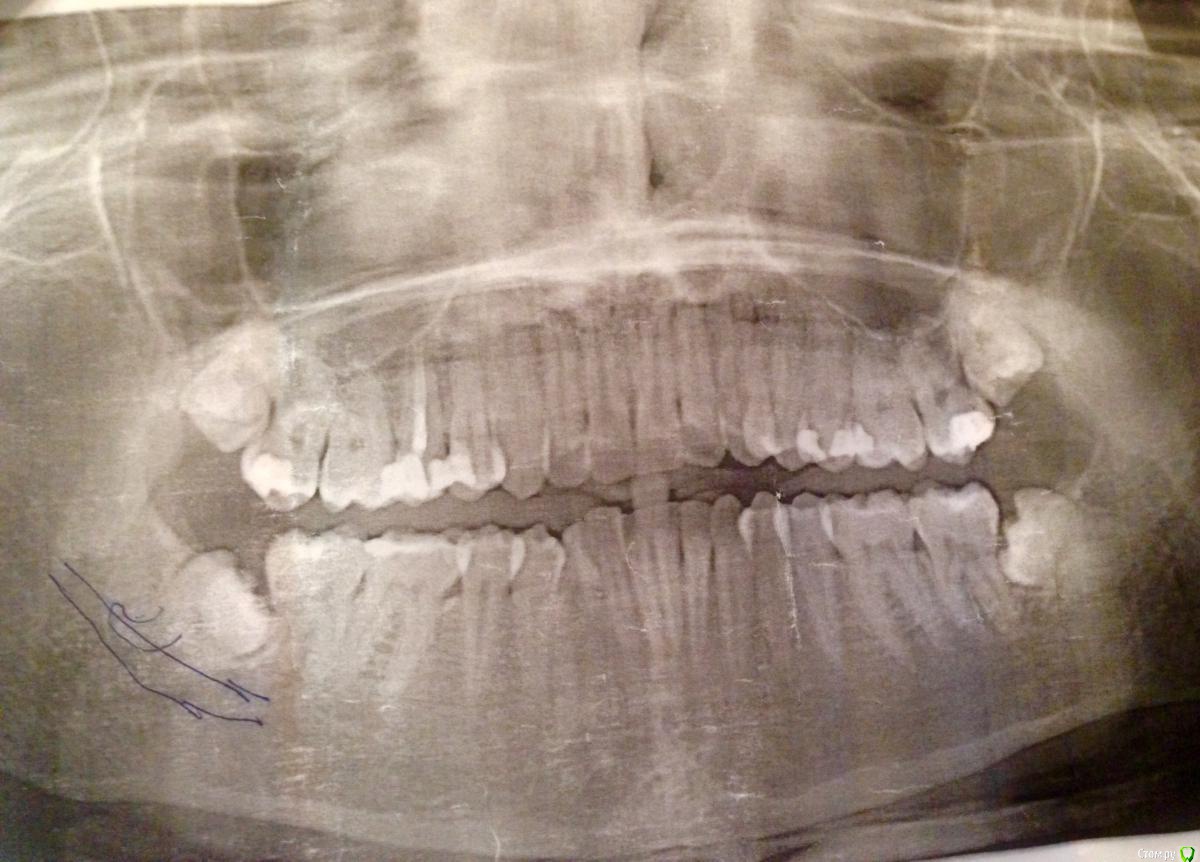

Chinaswallow Опубликовано 30 марта, 2017 Поделиться Опубликовано 30 марта, 2017 Добрый день!интересует, нужно ли удалить нижние восьмерки? они не прорезываются, не болятпо кт хирург сказал, что они лежат на челюстном нерве и возможен парез и что себе бы он такого делать не сталесть ли по ним угроза для 7-ок?что делать? удалять все-таки или нет? как быстро это надо сделать? будет ли парезмне 30 летверхние стали прорезыватьсяскученность зубов была в нижней челюстиприкус не правильный, из-за чего я думала, что этого не видно и это не страшнов приложении снимок и есть еще кт, попробую загрузить( не грузятся эти файлы) Ссылка на комментарий

red_butler Опубликовано 30 марта, 2017 Поделиться Опубликовано 30 марта, 2017 интересует, нужно ли удалить нижние восьмерки? все удаляйте по кт хирург сказал нам Кт покажите есть ли по ним угроза для 7-ок? есть есть еще кт, попробую загрузить( не грузятся эти файлы) выкладывайте срезы зон интереса, весь архив мало кто качать станет. Ссылка на комментарий